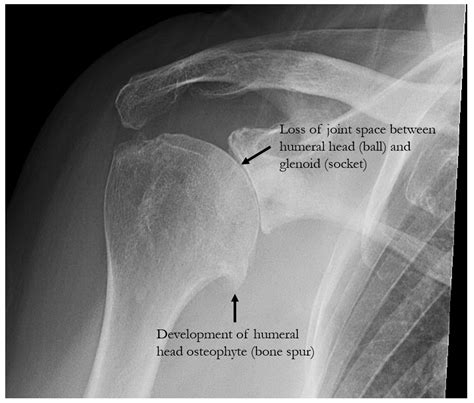

UW Shoulder and Elbow Academy: How bad is the shoulder arthritis on x-ray?

Learn what to expect during a shoulder X-ray. This guide explains how this diagnostic imaging procedure identifies fractures, dislocations, or arthritis. Discover how medical professionals use these X-ray images to assess joint health, evaluate bone structures, and determine the best treatment plan for your shoulder pain or injury. Optimize your preparation for an accurate clinical diagnosis today.